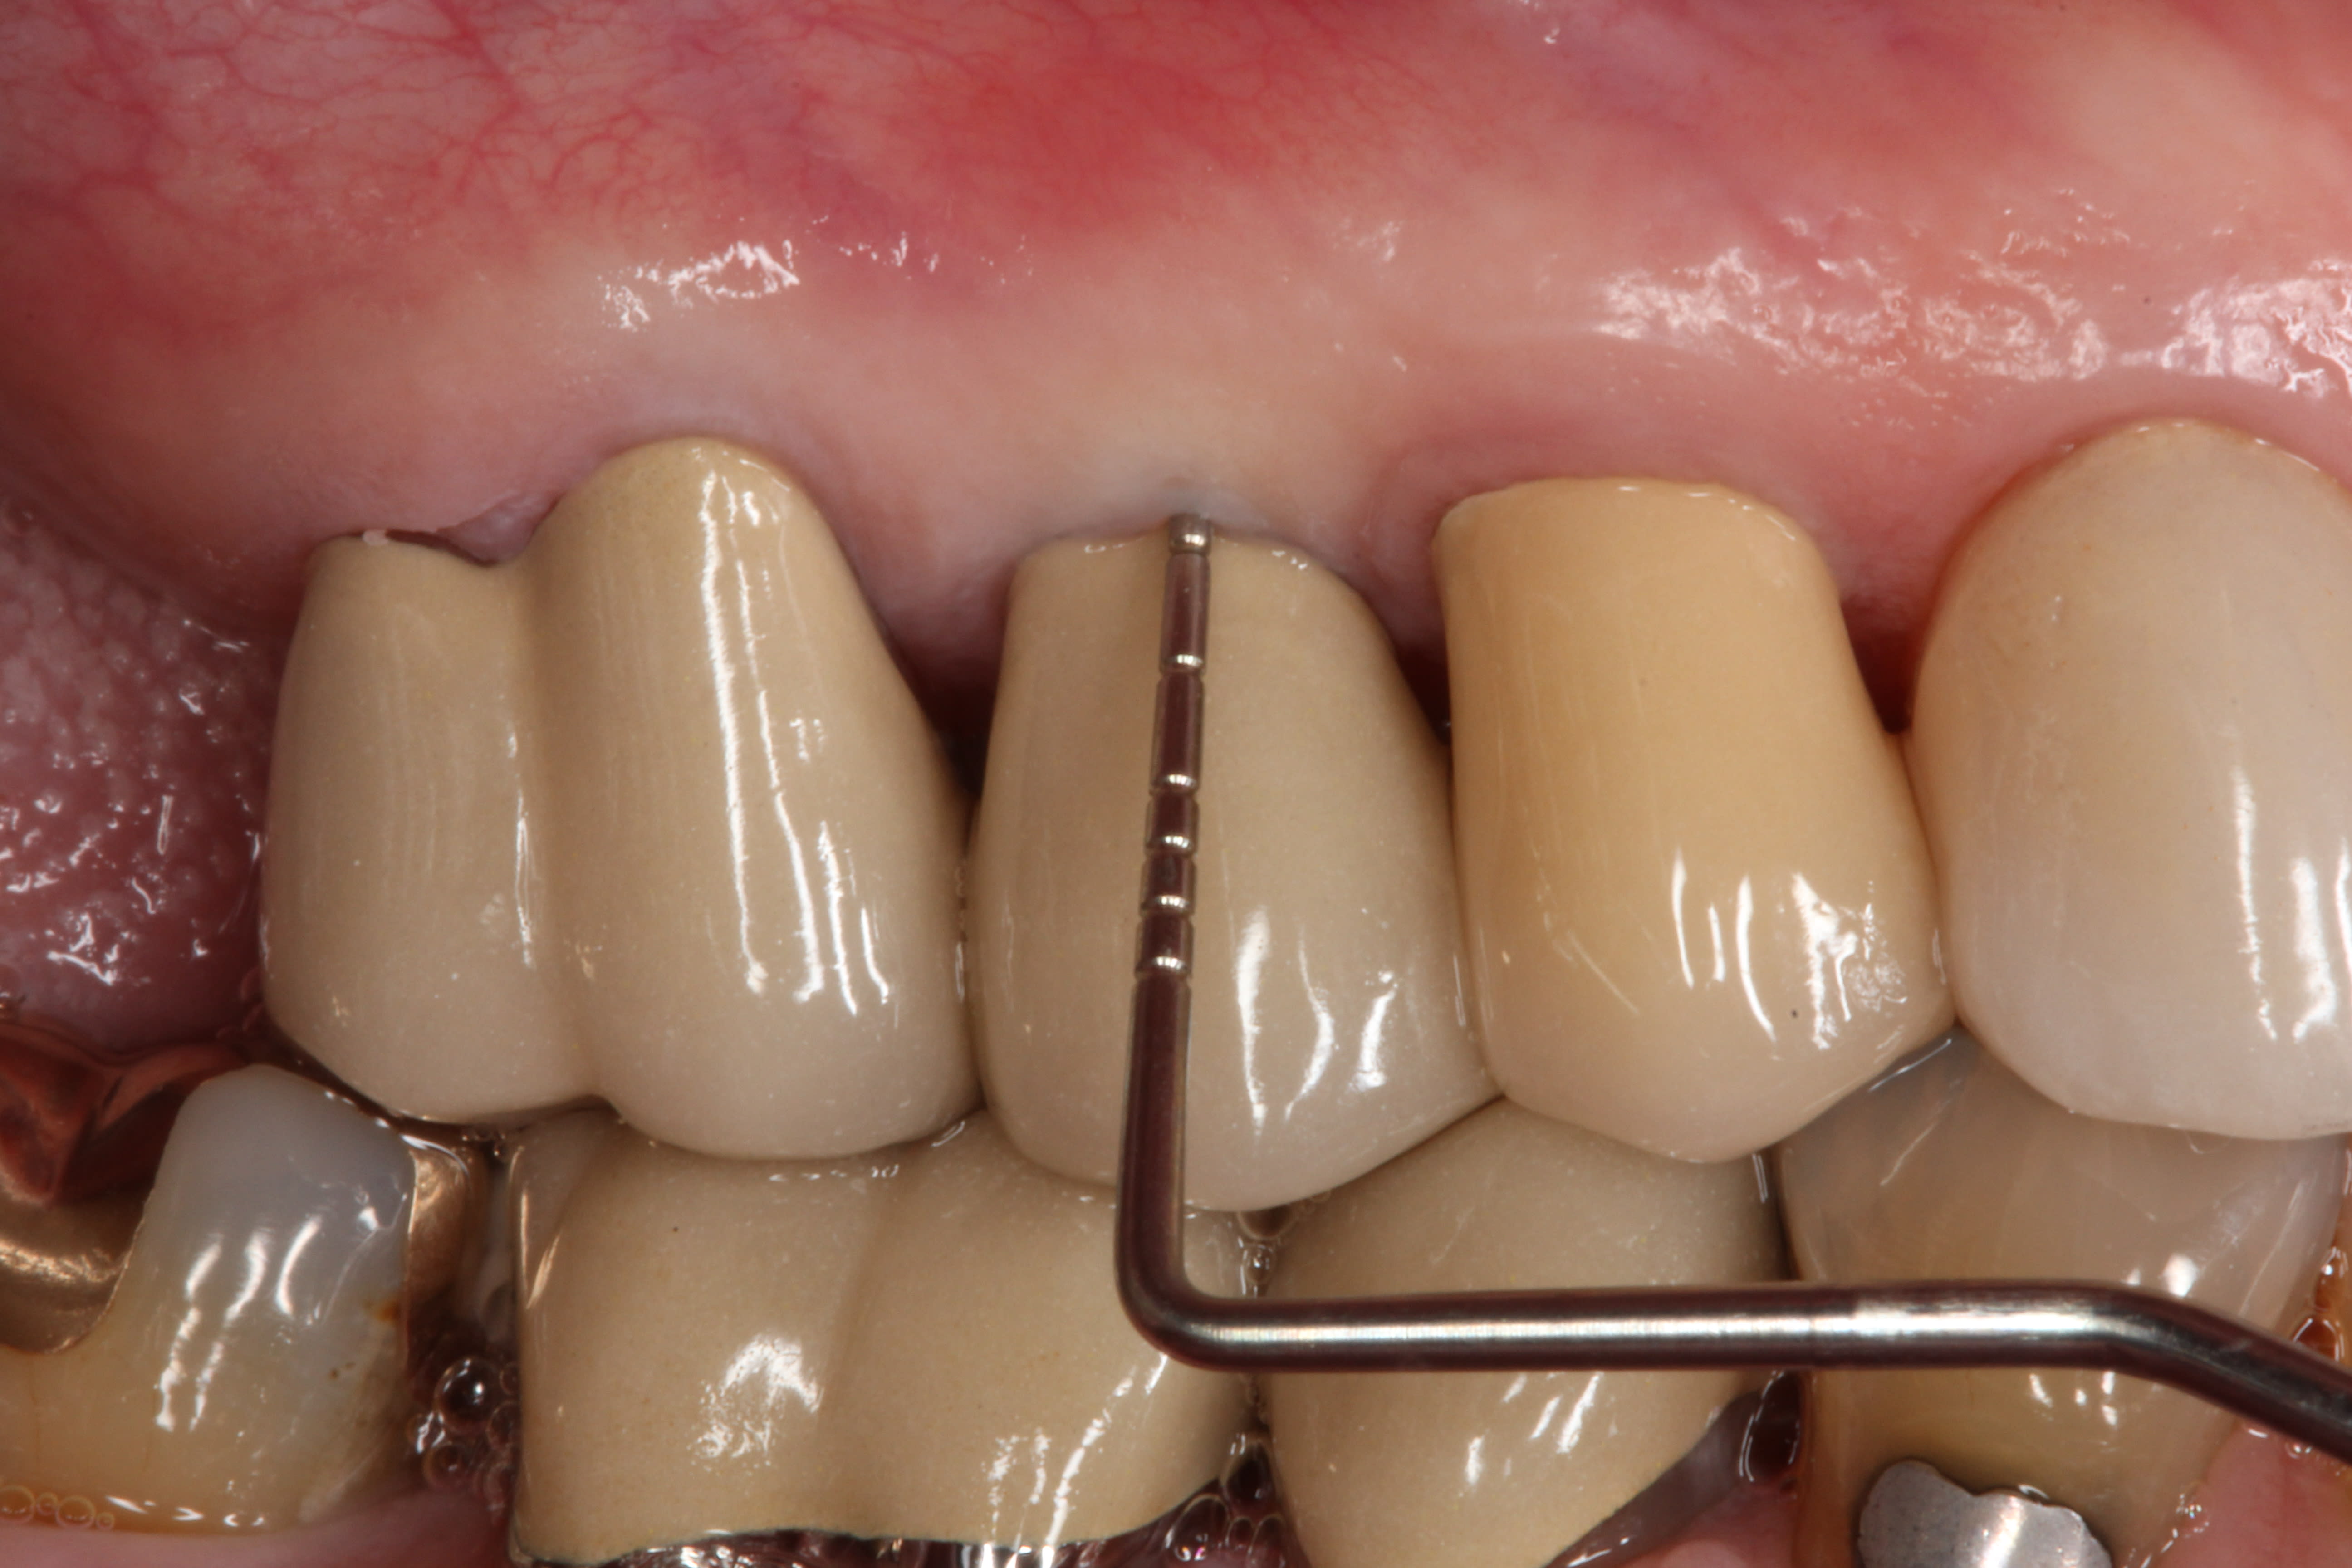

The final impression (closed tray) was obtained in April 2012. The final ceramic crowns (IPS e.max Ceram) and custom porcelain-veneered, regular-diameter (RD) UCLA abutments (Genesis; and Creation CC, Jensen Dental, www.jensendental.com) (Figure 24, shown with PFM crowns and retention screws) were delivered in May 2012. Using a platform-switched connection, the abutments were torqued to 30 Ncm, the access holes sealed with Teflon, and the final crowns cemented with RelyX Unicem. Figure 25 through Figure 28 show the final IPS e.max Ceram crowns from periapical, facial, and incisal views, with a midfacial PD of 3 mm at the 18-month follow-up (Visit 7). A thick biotype is evident in Figure 26, as determined by the inability to detect the outline of the periodontal probe inserted below the restoration’s gingival margin.50 This image also demonstrates an excellent esthetic outcome.

Although Case 3 showed an 18-month PD of 3.5 mm on the facial aspect of implant position No. 9 (the greatest PD recorded at this timepoint), good gingival tone and excellent esthetics were also evident at this visit (Figure 26).

Against such a backdrop of “ideal” case selection, it should be noted that no clinical scenario presented, neither in this case series nor in the earlier one from this multicenter study,11 captured all of these criteria, and, in fact, the cases displayed a challenging range of clinical variations that probably better approximates the clinical reality of interdisciplinary esthetic implant practice. Based upon clinical observations, all of these patients had relatively thick biotypes, with facial gingival thickness ≥2 mm through which a periodontal probe could, at most timepoints, not be visualized50 (exceptions were Case 3 at Visit 2, and Case 5 at Visit 6), including the 18-month assessment (Visit 7).